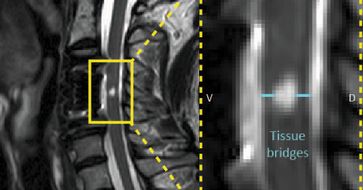

Emmenegger Tim; Development and Application of Quantitative MRI Processing Tools to Track Structural and Functional Changes along the Neuraxis Following Spinal Cord Injury; Universität Zürich; 2024

Schading-Sassenhausen Simon; Quantitative and Functional MRI Investigation of Neurodegeneration Associated with Spinal Cord Injury across the Neuraxis; ETH Zürich; 2024

Berroth Julia; Three-Dimensional Lesion Segmentation and Tract-Specific Damage Analysis in the Subacute Stage Following Spinal Cord Injury; ETH Zürich; 2024